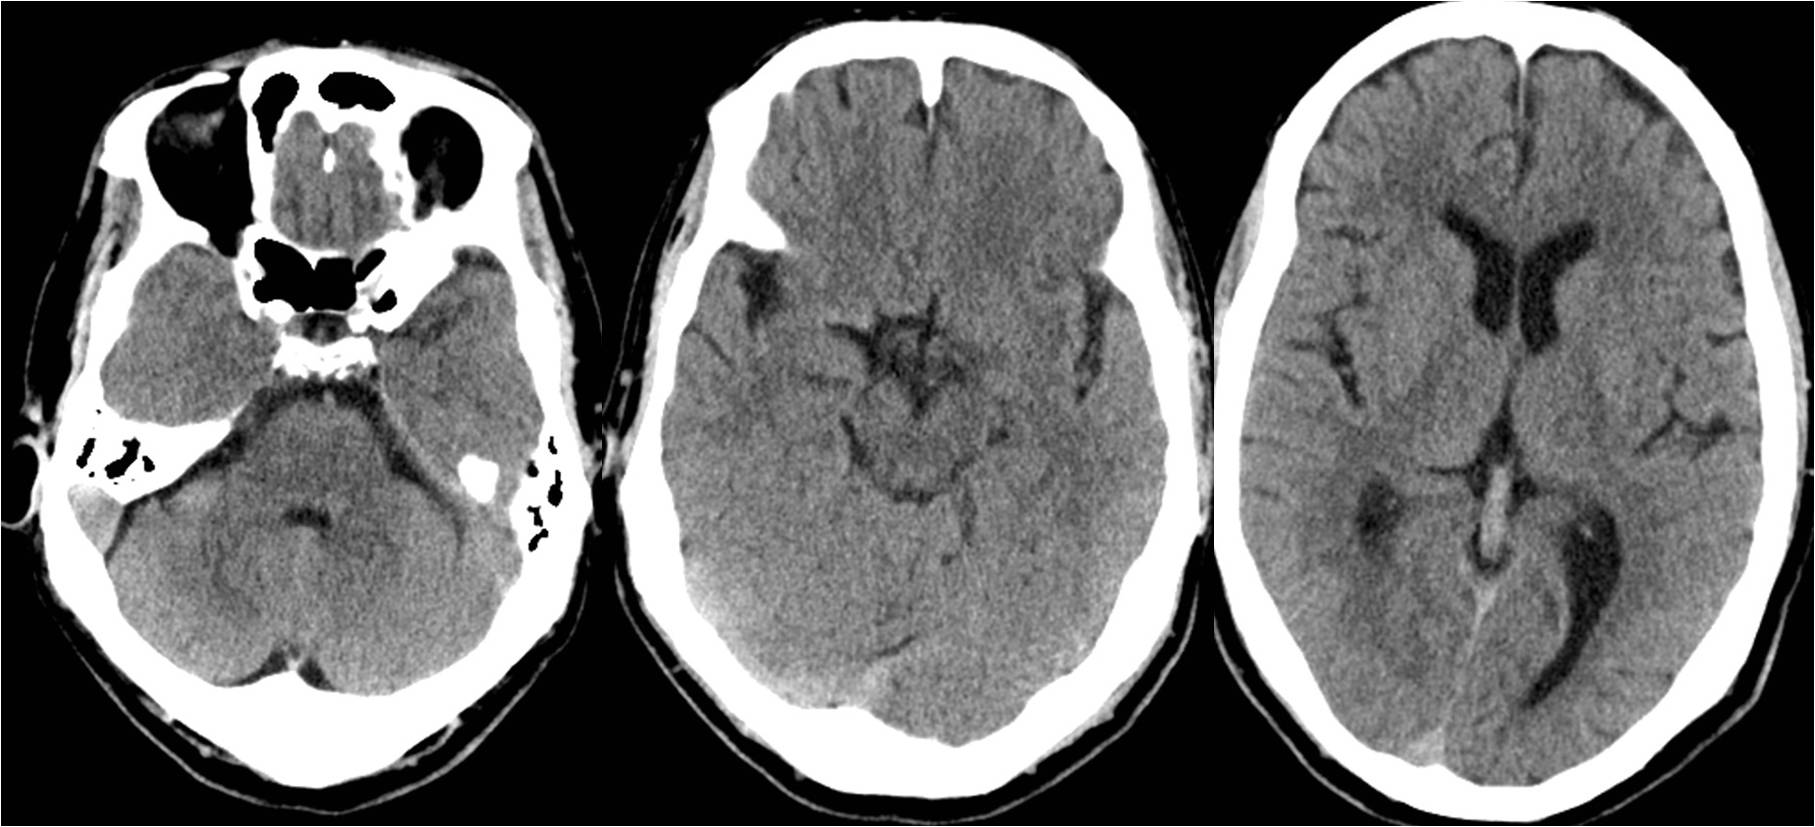

Case5 术后过度灌注、出血转化

》47岁,男,既往吸烟史20年

》12:00末次正常,15:00被发现言语不清、右侧肢体无力

》18:30到达急诊科,NIHSS 14分

》18:39完成头CT检查,19:28头MRA检查

》19:50行股动脉穿刺

》21:48结束手术

》术后24h NIHSS 8分

▼术前CT

▼术前MRA

▼术中给予替罗非班

▼术后24h头CT

▼术后72h 病情恶化,脑疝形成

▼去骨瓣减压,死亡